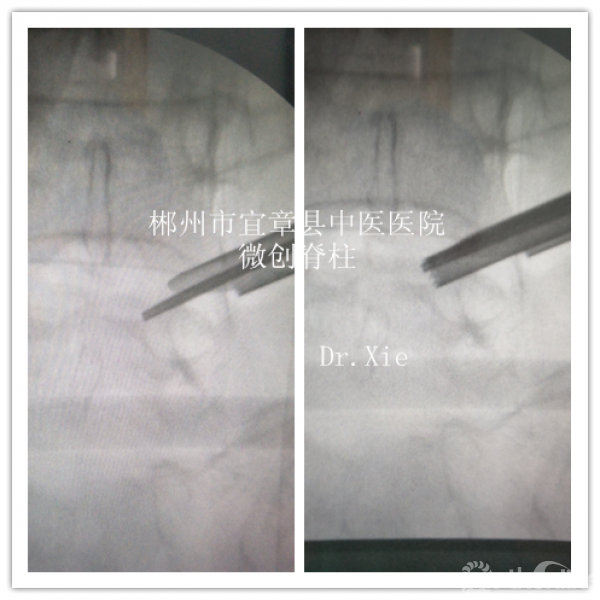

成型后置管透视情况